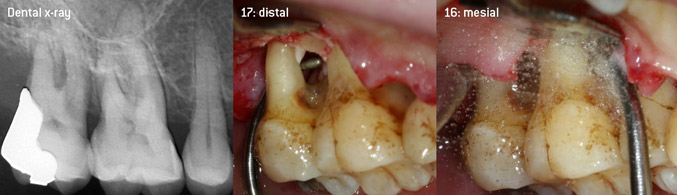

As initiators of the development of the new diamond-coated 3AP air scaler tip, the two dentists recognized the need for improvement of the handling restrictions of the commercially available diamond-coated tips, especially during furcation treatment and when working in tight intraosseous pockets. This should be possible for both non-surgical (Figure 2) and surgical (Figure 3) procedures.

(Fotos (Figures 2 -4): © Dr. Christian Graetz)